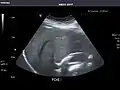

Liver

Ultrasonography of the liver with some standard measurements[6]

In patients with deranged liver function tests, ultrasound may show increased liver size (hepatomegaly), increased reflectiveness (which might, for example, indicate cholestasis), gallbladder or bile duct diseases, or a tumor in the liver.

Ultrasonography of liver tumors involves two stages: detection and characterization. Tumor detection is based on the performance of the method and should include morphometric information (three axes dimensions, volume) and topographic information (number, location specifying liver segment and lobe/lobes). The specification of these data is important for staging liver tumors and prognosis. Tumor characterization is a complex process based on a sum of criteria leading towards tumor nature definition. Often, other diagnostic procedures, especially interventional ones, are no longer necessary. Tumor characterization using the ultrasound method will be based on the following elements: consistency (solid, liquid, mixed), echogenicity, structure appearance (homogeneous or heterogeneous), delineation from adjacent liver parenchyma (capsular, imprecise), elasticity, posterior acoustic enhancement effect, the relation with neighboring organs or structures (displacement, invasion), vasculature (presence and characteristics on Doppler ultrasonography and contrast-enhanced ultrasound (CEUS).